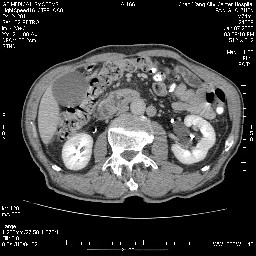

女,74岁,呕吐10余日

还有胃、脾之间可见有侧支循环建立。左肾盂积水。

双肾多发小囊肿;左肾积水。

十二指肠降段扩张,水平段狭窄成鼠尾状,肠壁明显增厚,胰腺勾突增大成不均匀强化,其内可见低密度区,胆囊增大,1十二指肠水平段腺癌侵犯胰腺勾突可能大,2胰腺癌侵犯十二指肠(只有胆囊增大没有肝内外胆管扩张不好解释)代除外.

十二指肠降段扩张,水平段狭窄成鼠尾状,肠壁明显增厚,胰腺勾突增大成不均匀强化,其内可见低密度区,胆囊增大,1十二指肠水平段腺癌侵犯胰腺勾突可能大,2胰腺癌侵犯十二指肠 。

今日手术结果:胰腺钩突癌侵犯十二直肠,腹腔淋巴结转移.